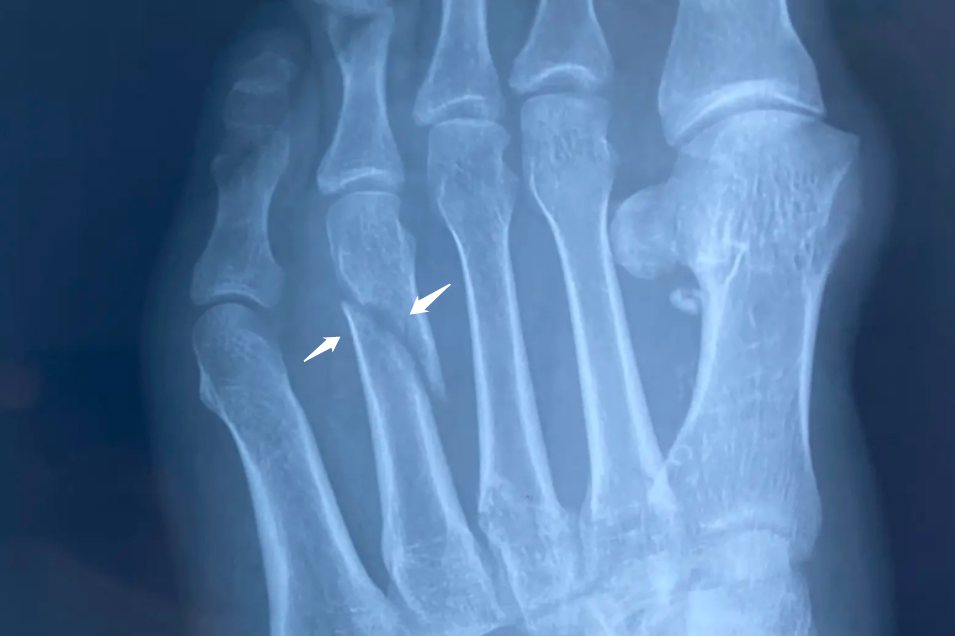

跖骨骨折十级伤残的重要临床表现为患足疼痛、肿胀,跖趾关节功能丧失,跖骨末节离断,X光片下可以看见的骨折断端和骨折移位。患足无法承受重力,触地行走或按压时骨折部位疼痛感觉明显加剧,患者行走困难。患者骨折愈合后不出现功能障碍。

下一篇:骨折照片是ct还是x光